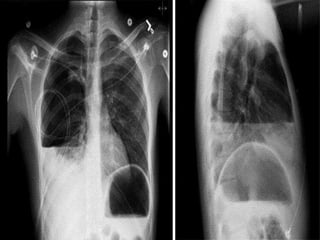

• Chest X- ray:

• 75 mL-subpulmonic space without spillover, can

obliterate the posterior costophrenic sulcus,

• 175 mL is necessary to obscure the lateral

costophrenic sulcus on an upright chest radiograph

• 500 mL will obscure the diaphragmatic contour on an

upright chest radiograph;

• 1000 ml of effusion reaches the level of the fourth

anterior rib,

• On decubitus radiographs and CT scans, less than 10

mL, and possibly as little as 2 mL, can be identified

Based on the decubitus films

• small effusions are thinner than 1.5 cm, moderate

effusions are 1.5 to 4.5 cm thick, and large effusions

exceed 4.5 cm.

• Effusions thicker than one cm are usually large

enough for sampling by thoracentesis, since at least

200 mL of liquid are already present